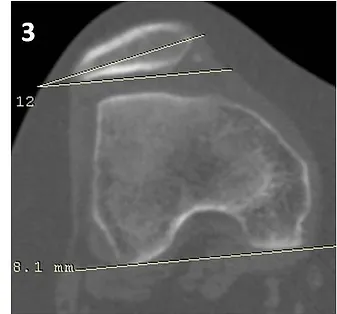

Figura 3’: Realizada avaliação da inclinação (“tilt”) patelar através da mensuração do ângulo da báscula.

Figura 3’: Realizada avaliação da inclinação (“tilt”) patelar através da mensuração do ângulo da báscula, estimado em 12° (normal <20°).